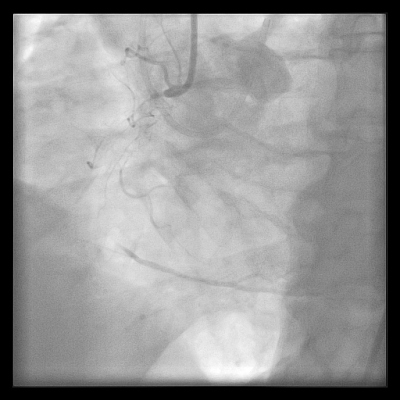

Rozsah koronárního postižení odpovídal střednímu rozsahu s hodnotou SYNTAX skóre II 20 bodů. Pacient byl dlouhodobě léčen jen pro hypertenzi a má nadváhu (body mass index 29,7 kg/m2), jinak je bez významných rizikových faktorů aterosklerózy. Postižení obou tepen bylo hodnoceno jako vhodné ke katetrizačnímu ošetření a po diskusi s pacientem byla na leden 2018 naplánována elektivní koronární intervence (PCI). Plánovanému zákroku předcházelo zahájení podávání duální antiagregace (kyselina acetylsalicylová v dávce 100 mg denně a clopidogrel 75 mg denně). Výkon byl proveden za použití dvou arteriálních přístupů. Do ústí pravé věnčité tepny byl zaveden katétr Vista JR4 7F (Cordis – Cardinal Health, USA) cestou pravého femorálního přístupu, do ústí levé věnčité tepny pak zaváděcí katétr Vista XB4 6F (Cordis – Cardinal Health, USA) pravým radiálním přístupem (obr. 4 a video 4).

Za podpory mikrokatétru Finecross a pomocí vodičů Fielder XT a Gaia Second (Asahi Intecc, Japonsko) byl proveden pokus o prográdní rekanalizaci standardní cestou (tzv. wire escalation technika), vodič Gaia Second prochází podél chronického uzávěru jen do disekce bez možnosti sondáže pravého lumen distálně od uzávěru (obr. 5 a video 5).

V dalším průběhu bylo přistupeno k rekanalizaci retrográdní cestou s využitím kolaterálního řečiště z RIA k periferii povodí ACD. Zaváděcí cévkou v ústí levé věnčité tepny byl po vodiči Balance Middle Weight (Abbott Vascular, USA) do úseku střední RIA zaveden mikrokatétr Corsair 150 cm (Asahi Intecc, Japonsko). Vodič byl vyměněn za hydrofilní rekanalizační vodič Sion Black a spolu s mikrokatétrem bylo proniknuto přes septální větev (obr. 6 a video 6)